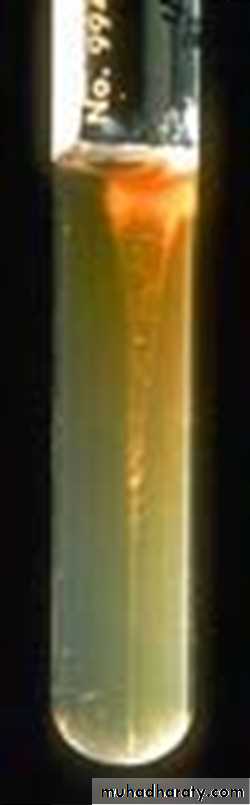

Gelatin liquefied, and

growth in gelatin stabsresembles an inverted fir tree

growth in gelatin stabsresembles an inverted

fir tree